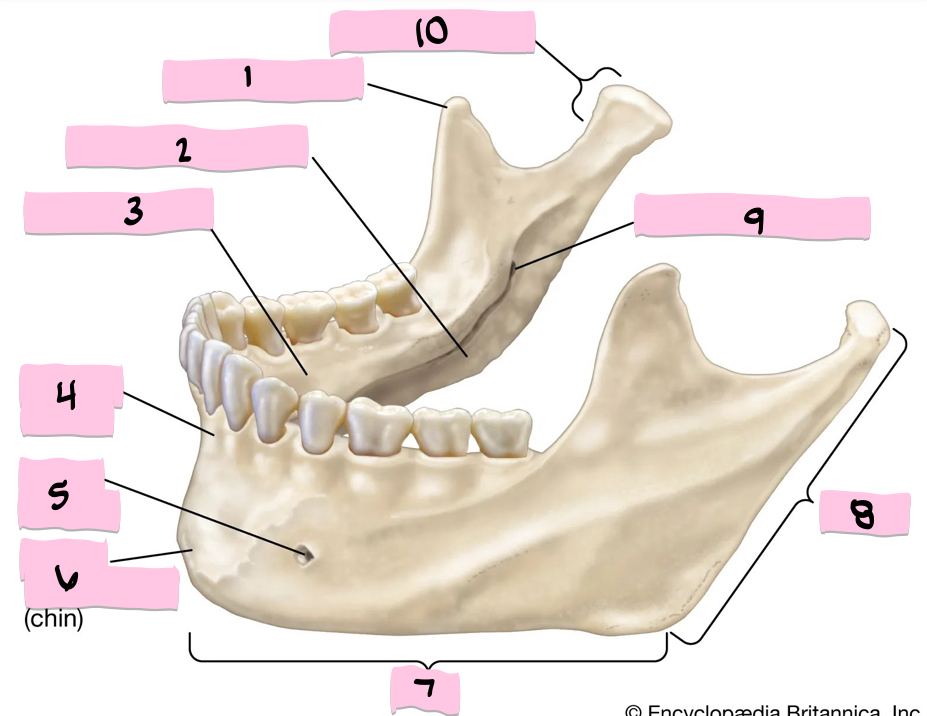

What is 1 pointing to?

Coronoid process

What is 2 pointing to?

Submandibular fossa

What is 3 pointing to?

Sublingual fossa

What is 4 pointing to?

Alveolar process

What is 5 pointing to?

Mental foramen

What is 6 pointing to?

Mental protuberance

What is 7 pointing to?

Body

What is 8 pointing to?

Ramus

What is 9 pointing to?

Mandibular foramen

What is 10 pointing to?

Condylar process